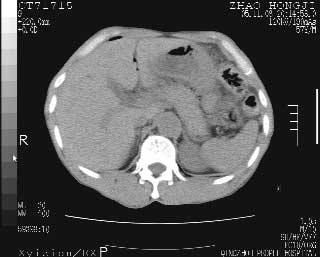

临床资料:男性,57岁,上腹部疼痛并5天,突然加重并延及全腹伴恶心5小时入院。胰淀粉酶化验在正常范围。检查:腹肌紧张,全腹压痛、反跳痛,尤以右上腹部为著。肠鸣音减低。血常规:wbc14.6x10/9, n:11.3x10/9 ,血压:135/90mmhg. 胸部透视:腹部肠腔轻度张气,未见其它异常改变。

肝右前缘少量积气,其他未见明显异常.考虑上消化道穿孔.

小网膜囊积气液,胃壁僵硬。考虑胃穿孔。

小膜网膜积液,肝缘气腹征,上消化道穿孔。

胰腺形态规则,胰周脂肪间隙清晰,结合临床可排除急性胰腺炎

从图提示我同意空腔脏器穿孔的诊断,来源肠道{由于病程较短,故没能见到肠系膜聚局的征象}。

肝缘见少许气体,胰尾部见少许气体包饶(蓝色圈),12指肠上部或球部邻近胆囊周边也可见少许气体影(黄色圈),并忖托出胆囊壁,12指肠远段肠道内未见明显气体(白色箭)。

肝脏前缘见少量积气、胰尾部见少许气体包饶,肾前筋膜未见增厚,临床淀粉酶不高,意见:上消化道穿孔。

消化道穿孔。12指肠球部周和胰周积气考虑12指肠穿孔可能性大。

入院3小时后行剖腹探查术,见腹腔内大量脓性混浊液约1000ml,十二指肠球部溃疡穿孔,溃疡面约2.5x2cm,穿孔直径约0.6cm。胃内容物外益,周围组织炎性水肿明显。行十二指肠穿孔修补术。术后诊断:

1、十二指肠溃疡穿孔

2、弥漫性腹膜炎

对于少量的腹腔游离气体,ct检查较普通透视有绝对的优势,它不仅可以看到肝脏前上缘的气体,而且还能够看到小网膜区的游离气体。从而可以肯定诊断。各位分析战友的很好,感谢大家的参入!